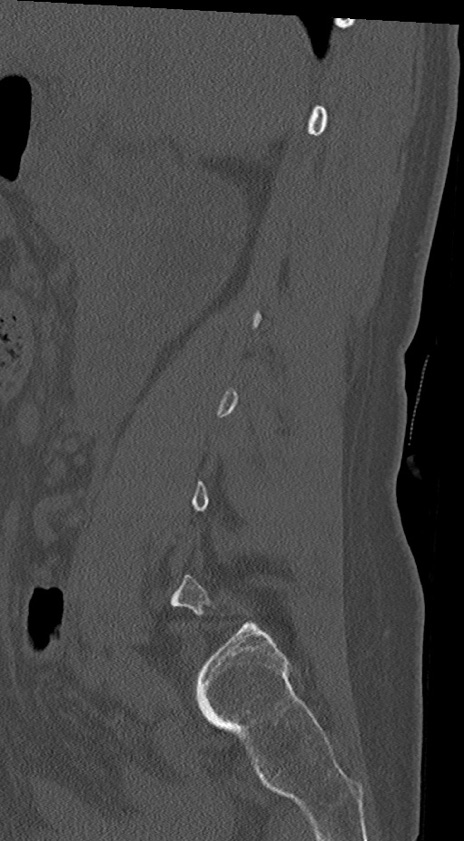

腰椎CT

冠状断像